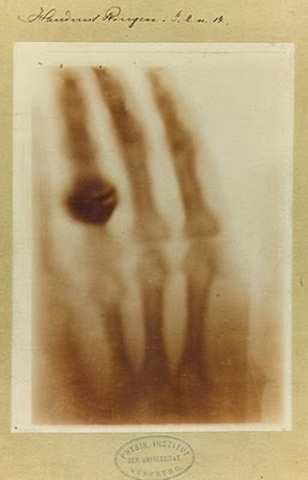

• La primera imagen radiográfica al cuerpo humano.

La primera imagen radiográfica al cuerpo humano.

Wilhelm Conrad R. le pidió a su esposa que colocase la mano sobre la placa durante quince minutos. Al revelar la placa de cristal, apareció una imagen histórica en la ciencia. Los huesos de la mano de Berta, con el anillo flotando sobre estos.